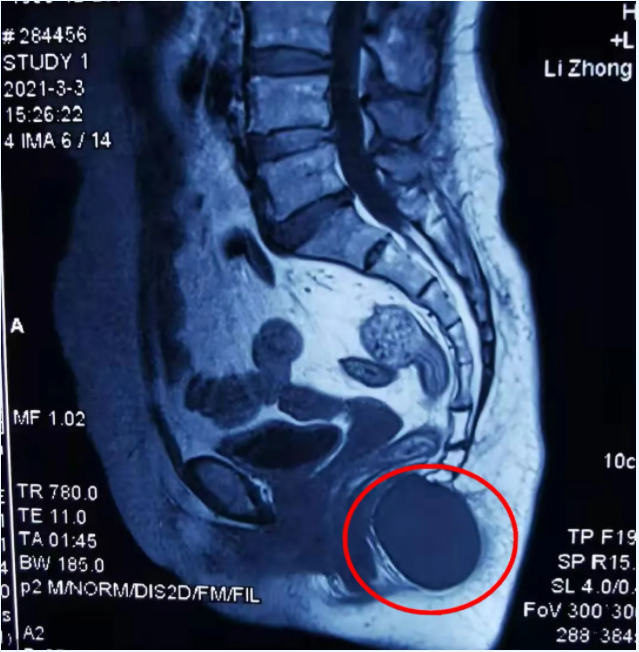

曾女士在家人的陪伴下辗转多家医院,均考虑是混合痔,但吃了一段时间治疗痔疮的药后也未见好转,直到在市内一家医院做了核磁共振检查,看结果才发现曾女士的尾椎下方有一个4cm*4cm如鸡蛋大小的肿块,已经压迫到直肠和骶尾神经,必须马上进行手术切除。但由于肿块太大,周围的神经、血管丰富,手术难度相当大,辗转几家医院都不敢为她动手术,此时曾女士更急了……

曾女士的亲戚得知这个情况,抱着试一试的态度带她来到娄星区人民医院(娄星区妇幼保健院)外科求医,入院后,曾女士进一步完善相关检查,初步诊断为“骶尾部后腹膜表皮样囊肿”,且肿块边界清楚,未侵犯周围软组织,良性肿瘤可能性大,肿块已由骶尾部延伸,通过尾骨尖端,进入盆腔,位置深,位于腹膜后直肠前,要完整切除肿块,术中很有可能损伤盆底重要血管,输尿管,盆腔及骶尾部神经等,病情比较复杂,手术切除非常困难。